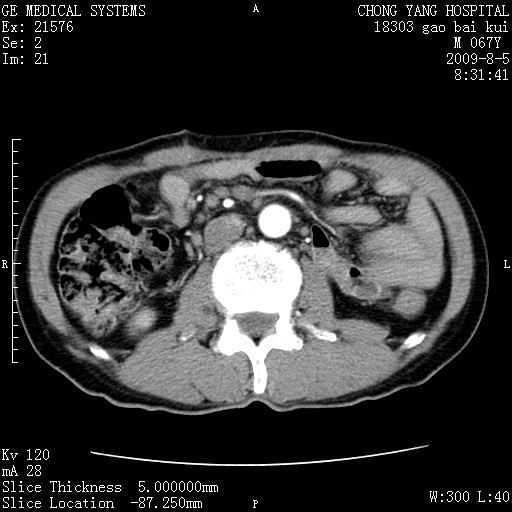

这个也过了,考虑胰腺钩突癌或壶腹癌,不除外胰管粘液乳头瘤伴胰管扩张,肝内胆管积气.

1)考虑胰头癌或壶腹癌并胰管扩张。2)肝外胆管扩张、积气,胆囊影未见;考虑术后改变。3)胃壁增厚?建议必要时行胃镜检查。

虑胰腺钩突癌或壶腹癌,不除外胰管粘液乳头瘤伴胰管扩张,肝内胆管积气.

考虑胰头癌并十二指肠受侵。